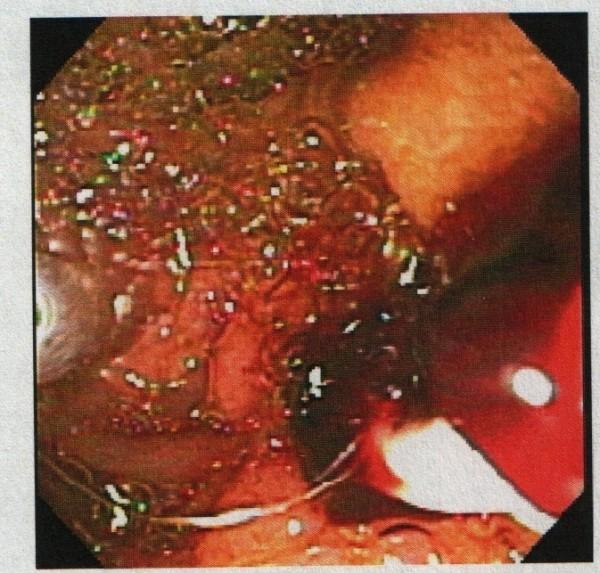

A 91-year-old African-American woman was referred to our out-patient gastroenterology clinic for evaluation of mild epigastric pain and intermittent melena. An abdominal computed tomography scan was remarkable for multiple hepatic cysts. Esophagogastroduodenoscopy revealed multiple blood clots at the ampulla of Vater. Endoscopic retrograde cholangiopancreatography showed a single 18 mm-sized filling defect in the common hepatic duct wall at the junction of the right and left hepatic duct, adjacent to one of the hepatic cysts. The ruptured hepatic cyst communicated to the bile ducts and was the cause of hemobilia with an atypical clinical presentation.

一名91岁的非裔美国女性因轻度上腹部疼痛和间歇性黑便被转诊至我们的门诊胃肠病诊所。腹部计算机断层扫描显示多个肝囊肿。食管胃十二指肠镜检查发现 Vater壶腹有多个血凝块。内镜逆行胰胆管造影显示在左右肝管交界处的肝总管壁上有一个18毫米大小的单一充盈缺损,与其中一个肝囊肿相邻。破裂的肝囊肿与胆管相通,是导致具有非典型临床表现的胆道出血的原因。